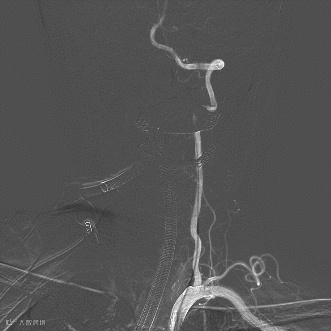

6F中间导管(6F 115cm,中天天巡远端通路导管)与6F NeuroMax长鞘同轴,在泥鳅导丝引导下,将长鞘送至左侧锁骨下动脉椎动脉发出处,将中间导管送至左侧椎动脉V4段起始(图5 A,B)。

图5(A)

图5(B)